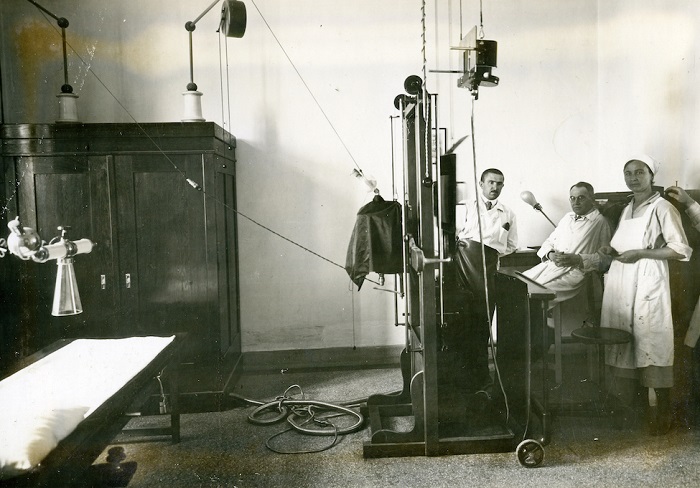

Izložba će predstaviti istorijski razvoj i primenu rendgenske tehnologije u medicini, od otkrića rendgenskih zraka do danas, sa posebnim naglaskom na doprinosima koji su u oblasti rendgenologije ostvarili Nikola Tesla i Mihajlo Pupin. Ciljevi izložbe su i predstavljanje uspeha domaćih preduzeća u razvoju proizvodnje rendgenskih aparata i opreme.

Pored fotografija i dokumenata, na izložbi će moći da se vide i stari rendgenski aparati, oprema i sredstva za ličnu zaštitu od zračenja, prve rendgenske cevi proizvedene u Jugoslaviji, ali i najnoviji digitalni rendgenski uređaji. Sastavni deo izložbe su sadržaji u obliku virtuelne stvarnosti (VR) i edukativne digitalne igre za decu i omladinu koje su kreirali najbolji polaznici besplatnih edukativnih programa za razvoj igara, prijatelja izložbe Nordeus Haba i Krater trening centra. Tokom trajanja izložbe biće organizovana stručna vođenja, predavanja i edukativne radionice za decu, omladinu i studente.